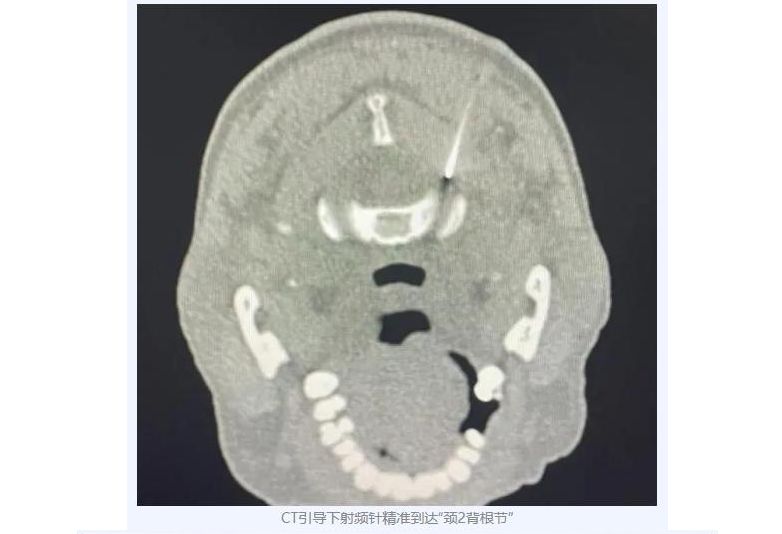

经多方辗转问医,她慕名来到哈医大四院疼痛科。周华成主任团队凭借丰富经验,为王女士实施了精准的颈2神经节诊断性阻滞。阻滞后,疼痛获得了明确的缓解。这一关键性反应精准“锁定”了困扰她20年的病根——颈2神经节功能异常,这是导致王女士顽固头痛的“罪魁祸首”。明确病因后,周主任及团队为其实施了CT引导下颈2背根神经节脉冲射频治疗。术后,王女士即刻感受到头部疼痛显著缓解,当日顺利康复出院。

颈源性头痛病因隐匿,极易误诊。王女士尝试多种疗法无效,关键在于未能精准识别“责任神经节”——颈2神经。对于这类患者,当保守治疗(药物、物理治疗、神经阻滞)效果不佳或反复发作时,CT引导下背根神经节脉冲射频治疗往往能取得让人满意的疗效:

高分辨率CT清晰呈现颈椎精细结构,穿刺针能够避开血管、神经和脊髓等重要结构,直达颈2神经节靶点。